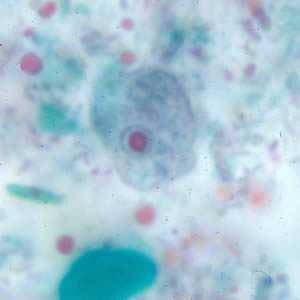

E. nana trophozoites stained with trichrome.

Figure A: Trophozoite of E. nana stained with trichrome.

Figure B: Trophozoites of E. nana stained with trichrome.

Figure C: Trophozoite of E. nana stained with trichrome.

Figure D: Trophozoite of E. nana stained with trichrome. Image courtesy of the Kansas Department of Health and Environment.

Figure E: Trophozoite of E. nana stained with trichrome.